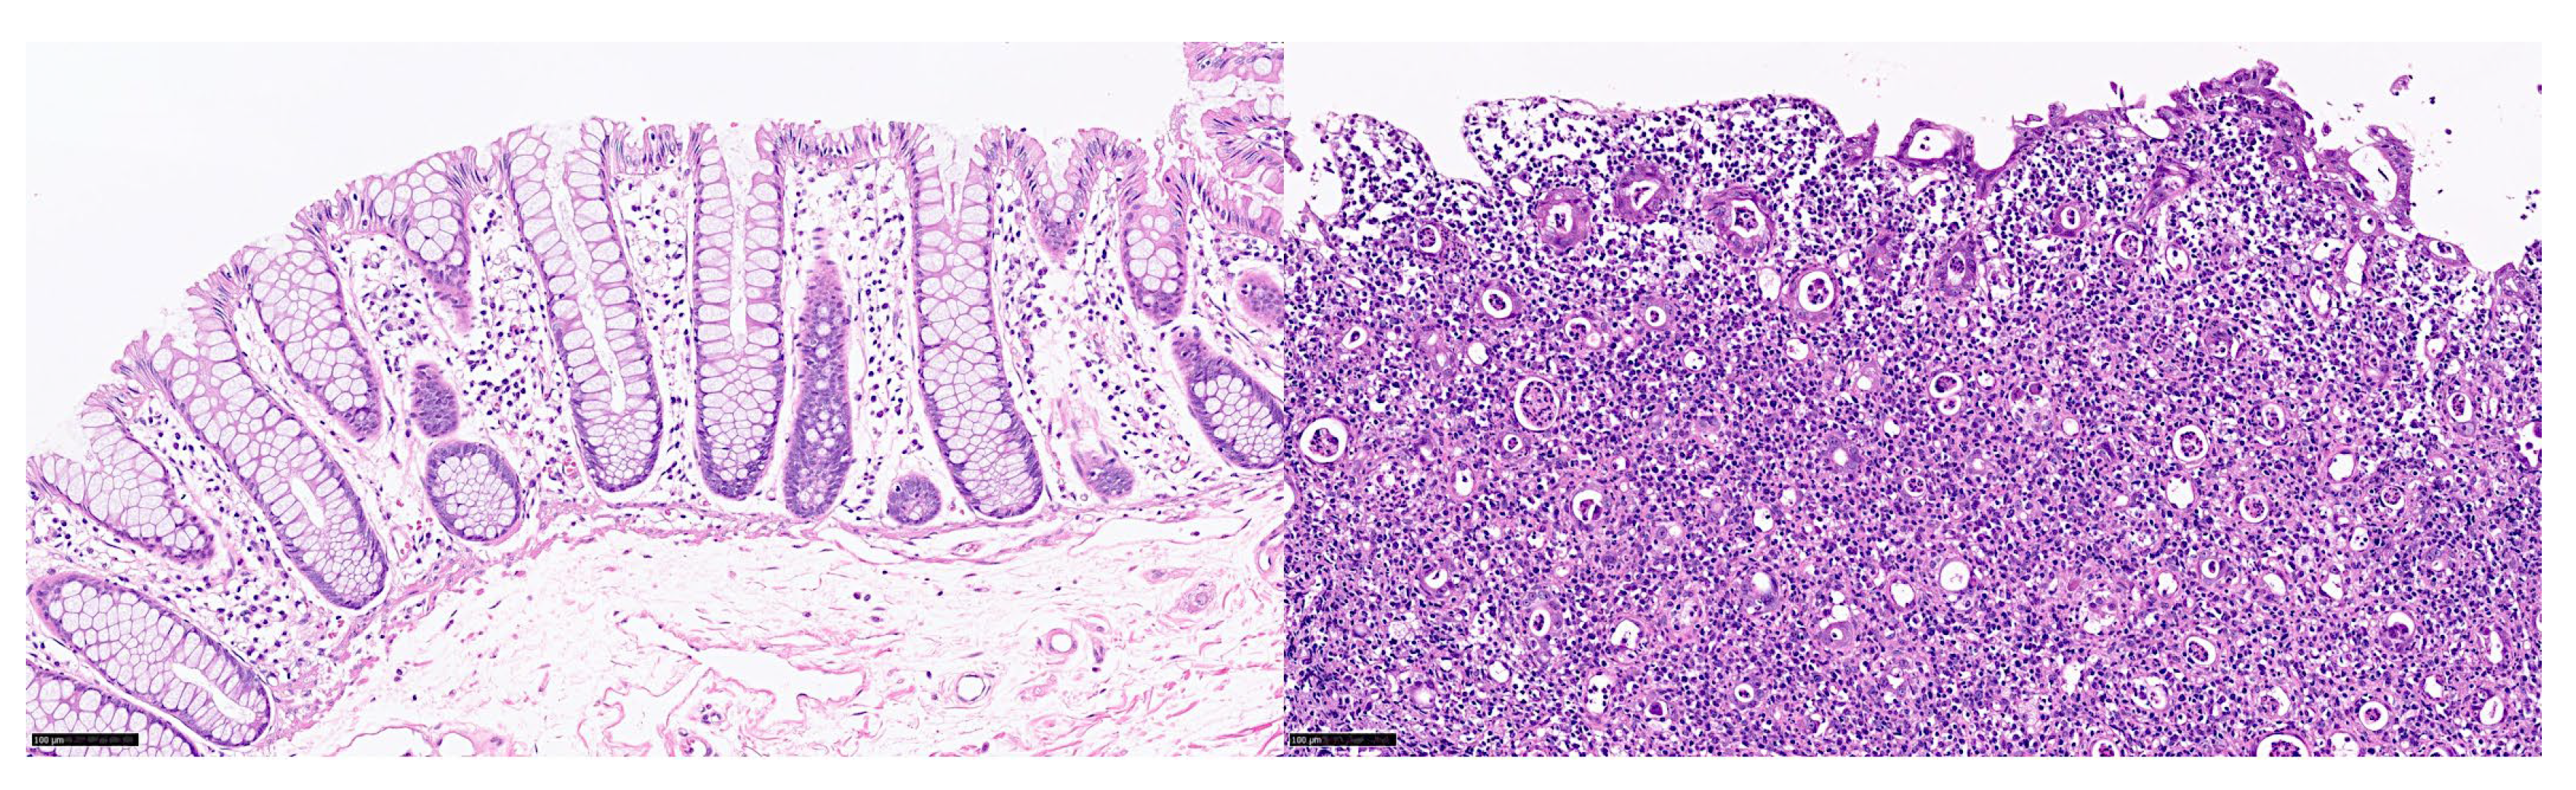

2. Data Description

5. Discussion